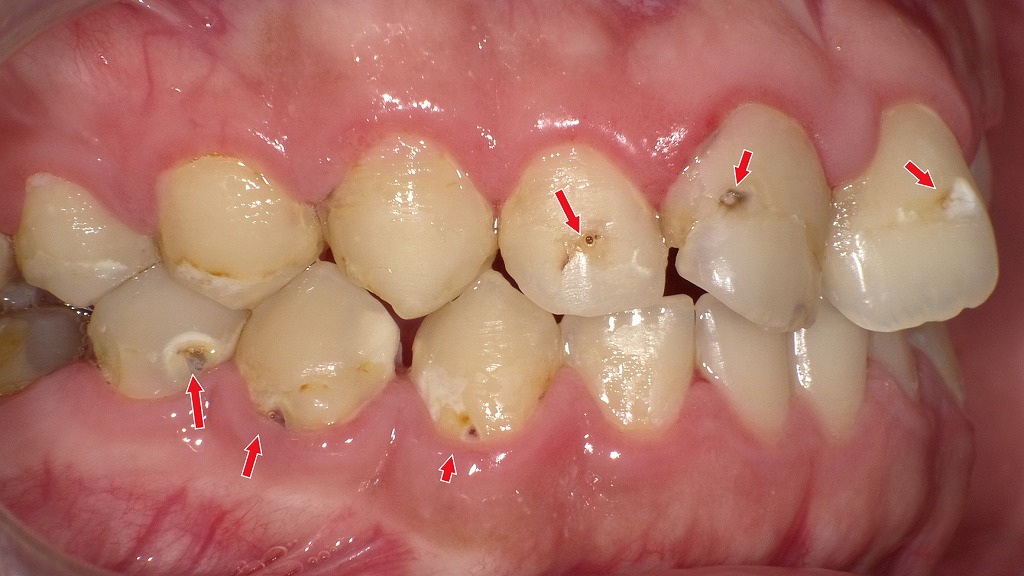

歯と歯の間の黒い点は要注意|レントゲンで発見できる“隠れ虫歯”

赤矢印が示すように、歯と歯の間(コンタクト部)の初期虫歯は、肉眼ではほとんど確認できません。レントゲンを撮影することで、エナメル質内部の透過像として虫歯を早期に発見できます。見た目に穴がなくても進行している場合があるため、定期的なレントゲン検査は非常に有効です。